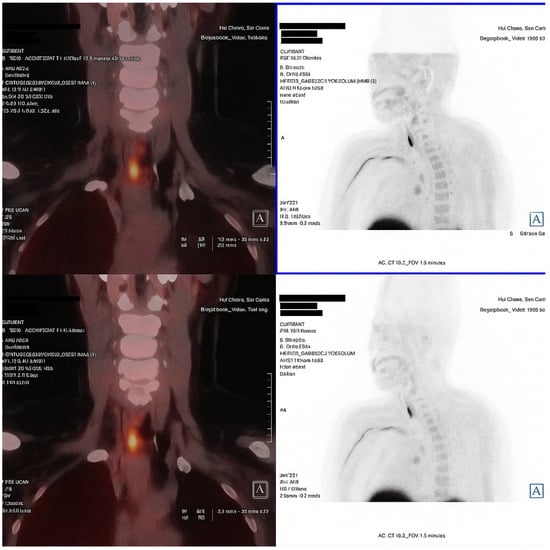

An 18F-fluorocholine PET-CT (18F-choline PET-CT) scan performed in November 2024 identified two right parathyroid adenomas, located in the upper and lower poles. The patient did not report renal colic, falls or new fractures. At the most recent follow-up, a diagnosis of PHPT was confirmed, characterized by hypercalcemia, persistent hypophosphatemia, elevated PTH and FGF-23 levels and absence of hypercalciuria or overt hyperphosphaturia.

Secondary causes of hyperparathyroidism, including vitamin D deficiency, chronic kidney disease, and malabsorption, were excluded, thereby supporting the diagnosis of primary hyperparathyroidism (PHPT) (Figure 1).

In this case, hypophosphatemia was an early biochemical finding that persisted for nearly a decade, preceding the development of the classic biochemical profile of primary hyperparathyroidism. The patient was referred for surgery.

Figure 1. Fused coronal and axial images (left) and anterior projection MIP sections (right) identify two areas of focal increased uptake in the right cervical region. The uptake corresponds to a posterosuperior nodular lesion and an inferoposterior nodular lesion adjacent to the right thyroid lobe, findings consistent with double right parathyroid adenomas (superior and inferior). This technique localized the parathyroid adenomas, eliminating the need for FDG-PET to exclude oncogenic osteomalacia.